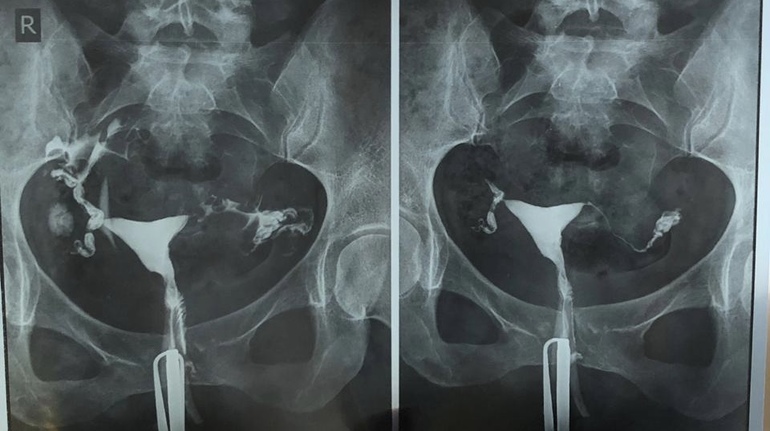

Медицинские снимки: Проходимость маточных труб